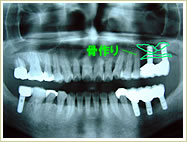

症例 68歳 女性 インプラント埋入数:1個 4本 画像拡大

治療前 治療後